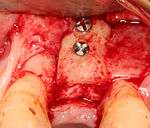

An incision is made across the area and the flap of gingiva is opened to show the bone of the jaw.

An incision is made across the gingiva, and the flap of tissue is reflected to show the bone of the jaw.

A series of slow-speed drills create and gradually enlarge a site in the jaw for the implant to be placed. The hole is called an osteotomy.

Once the bone is exposed, a series of drills create and gradually enlarge a site (called an osteotomy) for the implant to be placed.

The implant fixture is turned into the osteotomy. Ideally, it is completely covered by bone and has no movement within the bone.